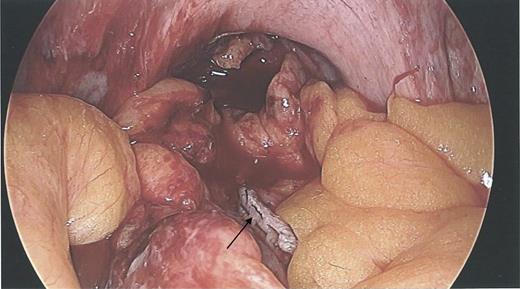

During the hysteroscopy 4 weeks later there was no evidence of an IUCD into the uterine cavity and no evidence of a perforation site in the uterus (Fig. 1). A laparoscopy followed, locating the coil threads deep in the Pouch of Douglas, with the IUCD perforating through the sigmoid colon into the lumen (Fig. 2). The IUCD was retrieved laparoscopically and the defect in the sigmoid colon was repaired by stapling the tear (Fig. 3).

Hysteroscopy showing a normal endometrial cavity, no evidence of IUCD or site of perforation.